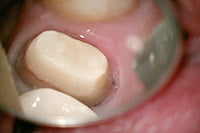

隔壁作成

隔壁作成まずは、隔壁を作成します。隔壁とは、唾液から根管への細菌感染を防ぐためと、根管治療で適切な薬剤を使えるようにするためのラバーダム防湿を行う為に作成する「壁」の事です。壁を作ることで、この先の治療が安全に確実に行えるようになります。なお、「隔壁作成」前に、被せ物・詰め物・土台・裏 層の除去が必要なことがあります。